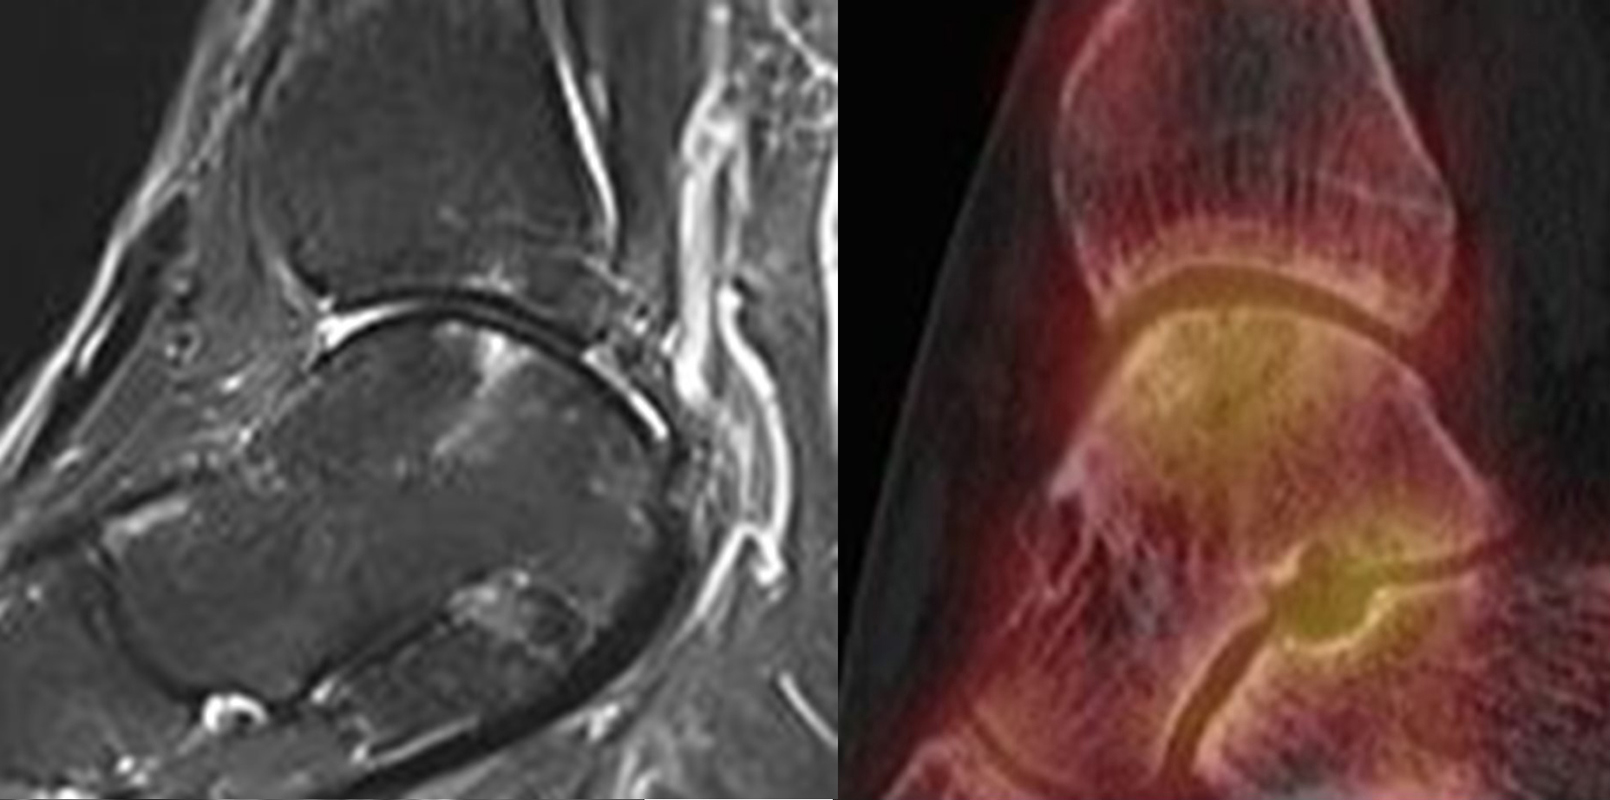

Die Abbildungen 4.2.a bis d zeigen den typischen Aspekt einer talacalcanearen Coalitio. Es besteht nur eine linksseitige, symptomatische Coalitio talocalcaneare (4.2.a und c); das 35 Tage zuvor angefertigte MRT zeigt keine auffälligen Signalveränderungen (4.2.b und d).

Coalitionen können auf Röntgenbildern wegen überlappender Strukturen häufig nicht sicher diagnostiziert werden, so dass MRT und/oder CT erforderlich sind, um eine Coalitio eindeutig nachzuweisen. Der Vorteil der SPECT/CT liegt darin, dass neben der submilimeter-genauen Darstellung der Anatomie, womit die charakterischten Röntgenzeichen einer Coalitio erkannt werden, auch die Stressreaktion bzw. die Scherkräfte, die auf die Syndesmose oder Synchondrose wirken, sichtbar gemacht werden können. Dabei hat die SPECT/CT eine deutlich höhere Treffsicherheit als die MRT zur exakten Lokalisation der Stressreaktion 44.